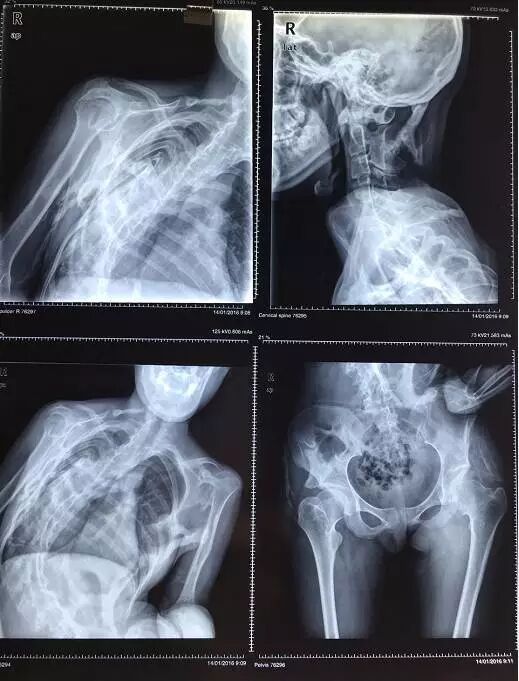

其他辅助检查:X 线照片显示肿物的软组织当中有分散钙化影。过一段时间,急性期的症状和体征消失后,肿物变小,钙化影也缩小,但密度增高。X 线片上可见柱状或不规则形态的团块状不同密度的骨化阴影,可与骨骼相连,也可完全游离。骨骼呈现失用性萎缩。

(FOP患者的X光片,异位骨化影响整个骨骼系统的形态,除局部的变形之外,脊柱也无法伸直)